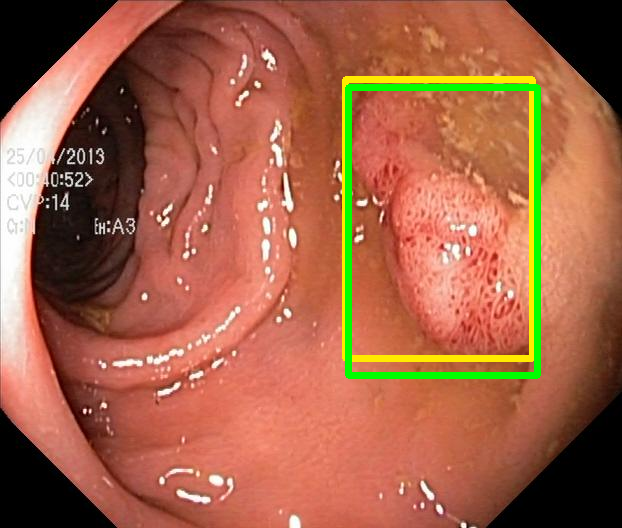

We evaluate the resulting object detection models using the test data, which is pre-processed in the same manner as the validation data, with AP@[.5:.95] (AP for conciseness), AP@.5 (AP50), and AP@.75 (AP75) computed for predicted bounded boxes with a confidence score \geq0.05. For all metrics, a higher value indicates better performance. The results are presented in Table VI, and some examples for predicted bounding boxes with a confidence score \geq0.5 are shown in Fig. 1.

Figure 1: Targets (yellow bounding boxes) and predictions (green bounding boxes) for two randomly selected instances of the Kvasir-SEG test set. For conciseness, we denote ResNet50s with RN, ViT-Bs with VT, Hyperkvasir-unlabelled with HK, ImageNet-1k with IN, MoCo v3 with MC, Barlow Twins with BT, MAE with MA, supervised pretraining with SL, and no pretraining with NA-NA.